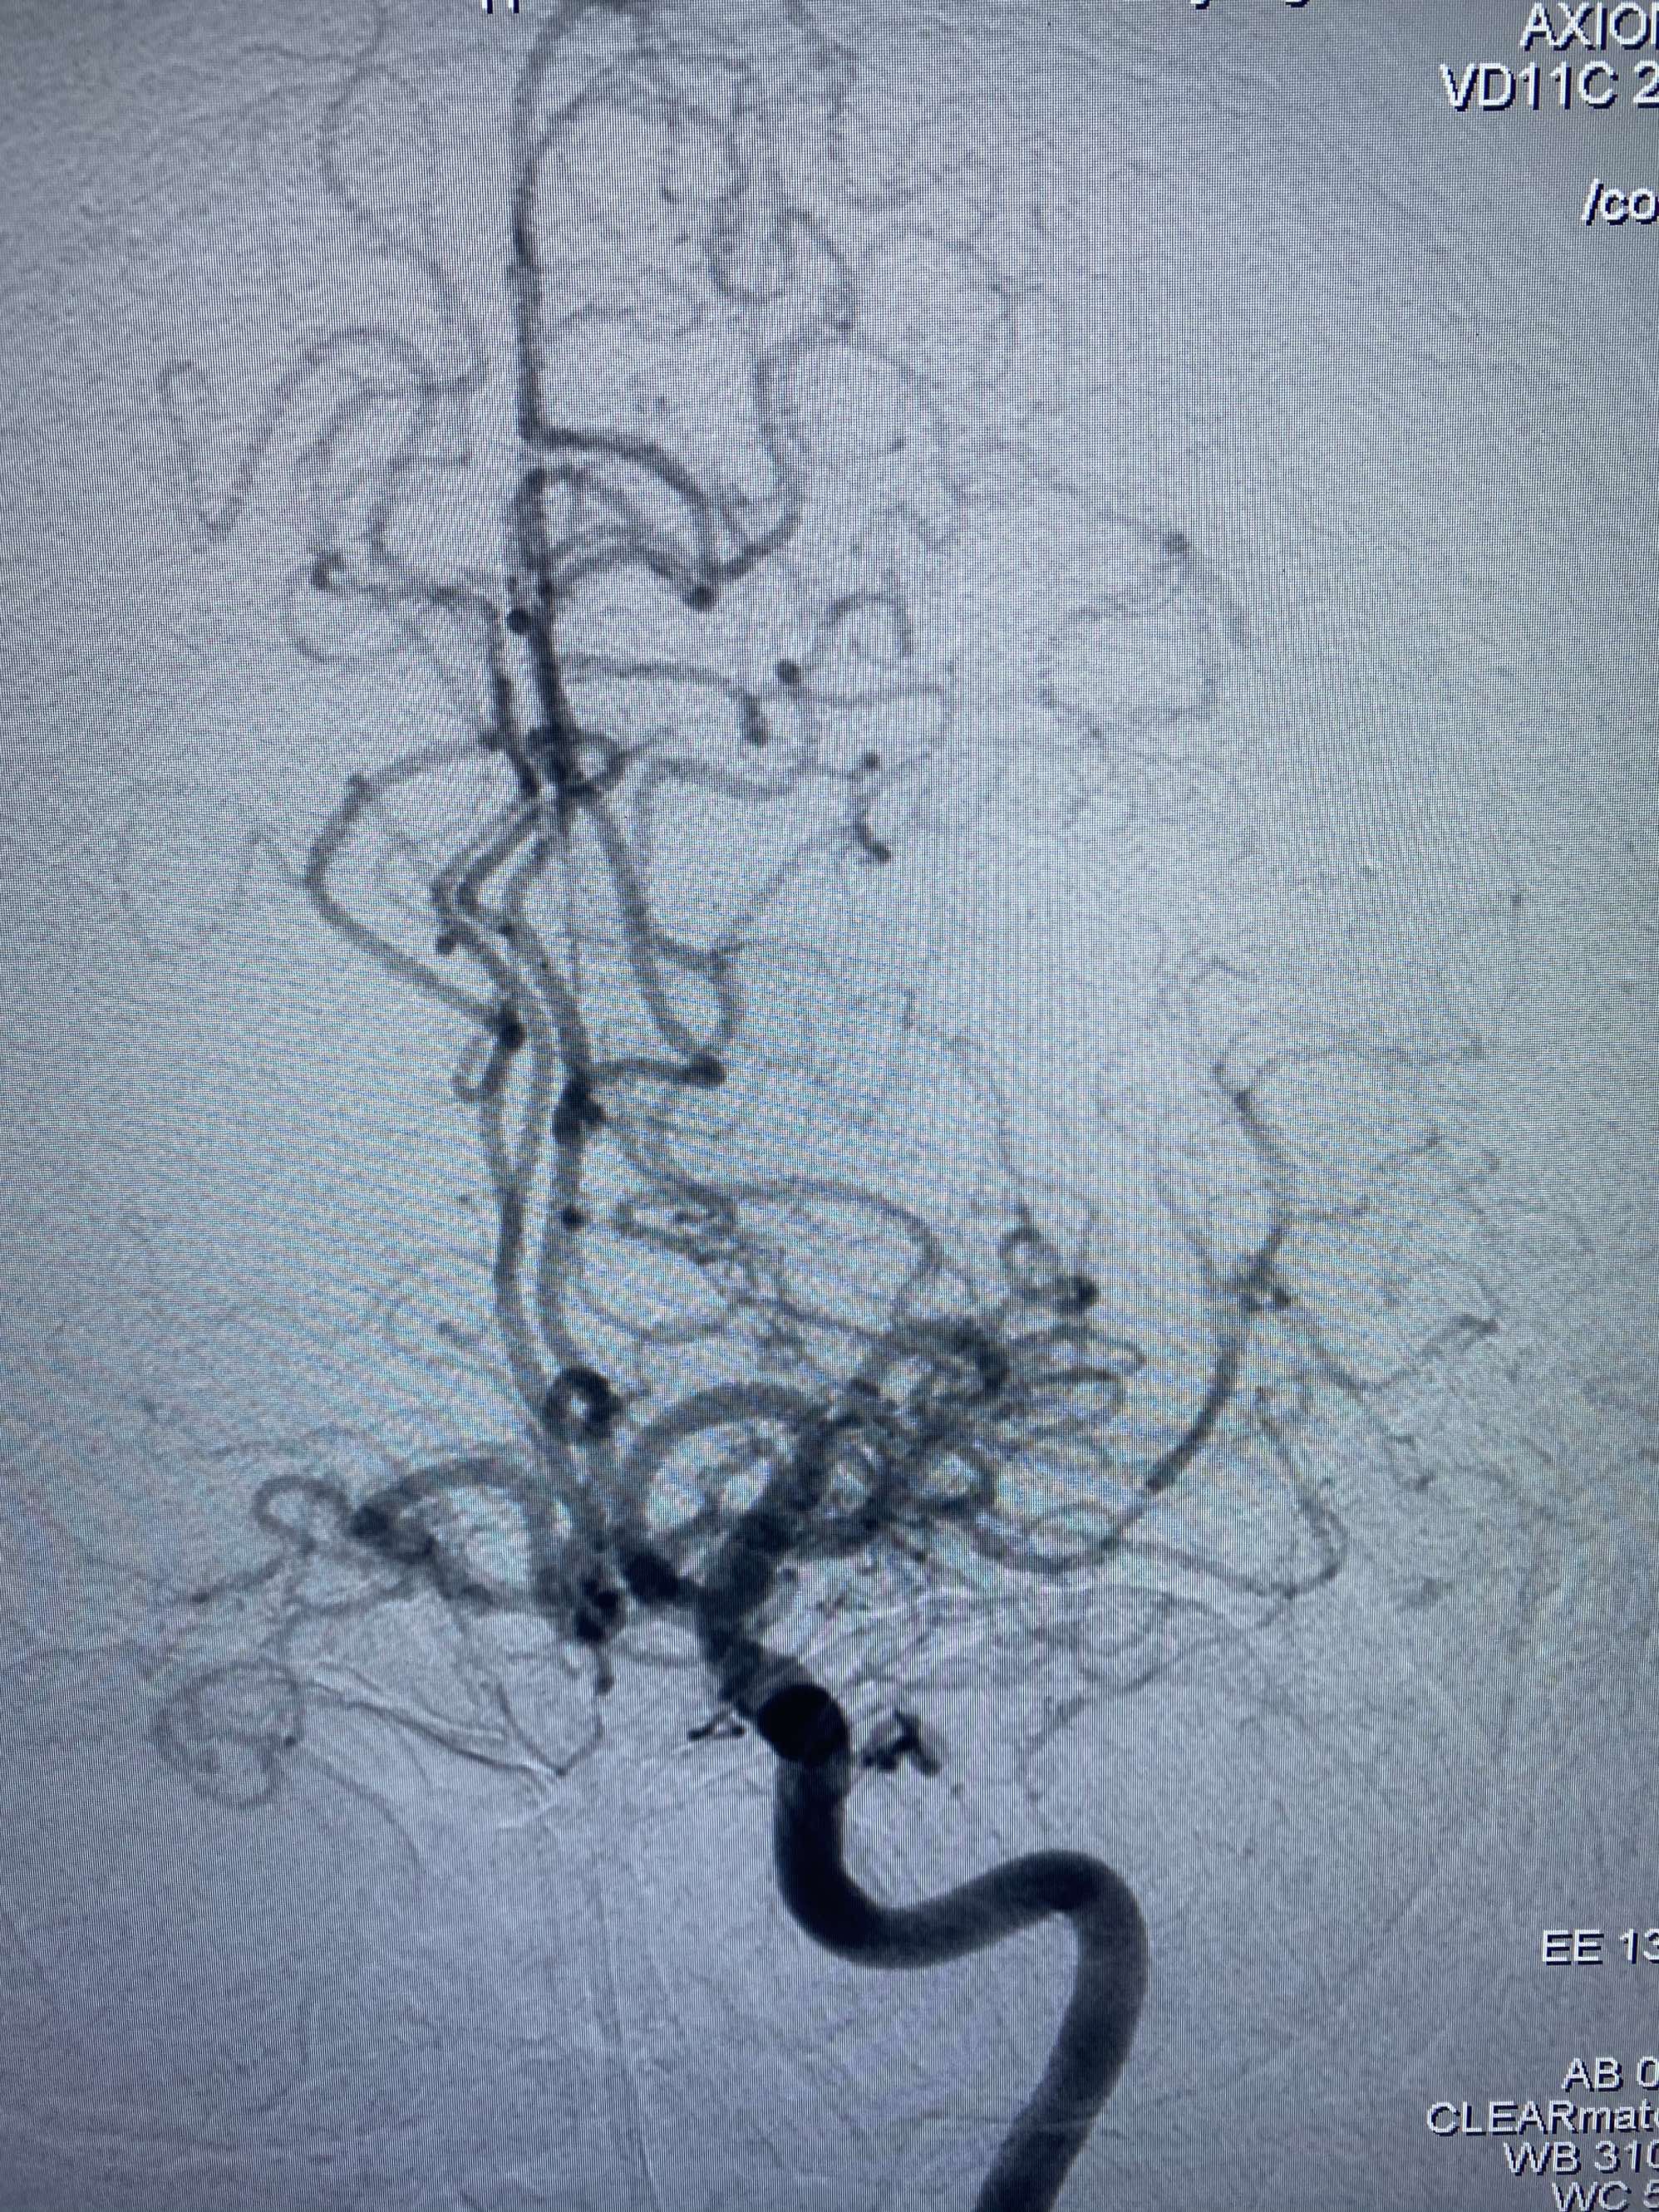

MLS,M79Y,sah,双侧MCA烟雾病,Heubner返动脉瘤,前交通段开窗,细支发出Heubner返动脉,瘤颈细长,瘤颈口比微导管细,弹簧圈2mmx3cm“隔山打牛”填塞治愈,Heubner返动脉保留。

该患者术后2天观察神志清楚,四肢活动正常。

Heubner返动脉是由大脑前动脉A1末端发出的豆纹动脉,由于走形和A1段相反,故称Heubner返动脉,该动脉梗塞可能引起尾状核头梗塞,引起偏瘫和面瘫,便身震颤等症状。